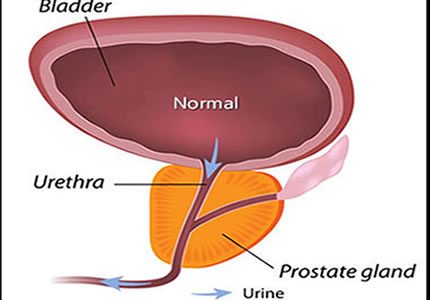

- A non-invasive, external measurement of the prostate. This provides a clear picture of the size and symmetry of the gland, helping to explain lower urinary tract symptoms in men.

- £150

- Ideal for: Men with urinary frequency or "stop-start" flow.